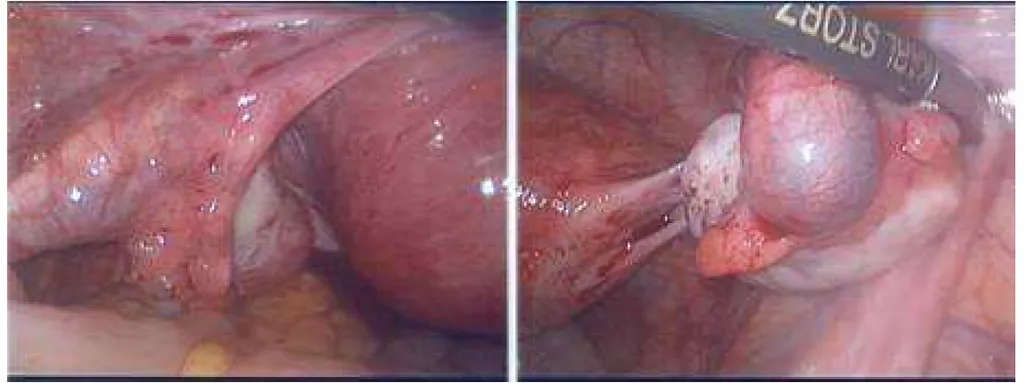

破題關鍵

這題的解題核心在於將臨床症狀、超音波發現與腹腔鏡影像結合判讀,特別是陽性懷孕試驗加上右下腹痛及腹腔鏡下輸卵管的異常腫塊,直接指向輸卵管外孕。圖片中右側影像清楚顯示右側輸卵管有明顯腫脹、發紺且有出血跡象的病灶,這就是典型的輸卵管外孕表現。